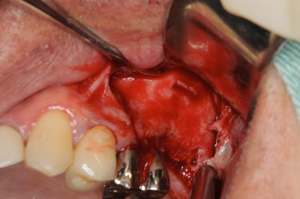

サイナスリフトをしている様子、横から骨を取り、上顎洞の粘膜を剥離していきます

粘膜が薄かったことが原因で粘膜が破れてしまい、サイナスリフトは中止、ここで

無理をしてオペをしてもいいことはないので、中止の勇断も必要です

4ヶ月後の患部、もう一度サイナスリフトをアプローチ

4ヶ月経つとこのように前回骨を削ったところもこのようにきれいに再生しています。粘膜も一度触っているので再生してことによって厚みがでて、剥離もしやすくなっています。